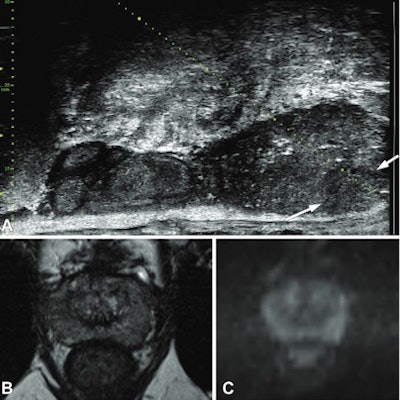

Multiparametric MRI is superior to transrectal ultrasound when it comes to detecting lesions in the prostate. By combining images from T2-weighted, diffusion-weighted, and dynamic contrast-enhanced protocols, and sometimes MR spectroscopy, the multiparametric method produces more detailed 3D images of the prostate gland than through conventional MRI.

Microultrasound operates at frequencies up to 29 MHz, and researchers have been looking into its potential for prostate cancer diagnosis. Microultrasound transducers have a fourfold higher crystal density, which makes for improvement of spatial resolution to as low as 70 mm, the size of a prostate duct. The investigators have also touted this method's higher sensitivity compared with transrectal ultrasound. However, microultrasound is also susceptible to interobserver variability in interpreting images.

Among 93 MRI targets, researchers found that 62 (67%) were prospectively visible on microultrasound.